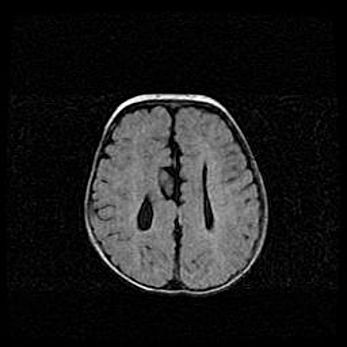

Множественные мелкие кисты перивентрикулярной области.

Киста прозрачной перегородки.

Возраст: 28 дней

Вес: 2400 г

Пол: женский

Окружность головы: 33 см

Срок гестации: 34 недели

Перивентрикулярная киста – это полостное образование в околожелудочковых областях белового вещества головного мозга. С морфологической точки зрения – это мелкоочаговая зона коагуляционного некроза, возникшая после инфаркта белого вещества. Наиболее часто поражаются начальные отделы задних рогов боковых желудочков. Обычно образования заполнены жидкостным содержимым.

Киста прозрачной перегородки может располагаться в переднем отделе межжелудочковой перегородки, в области мозолистого тела и мозжечка.